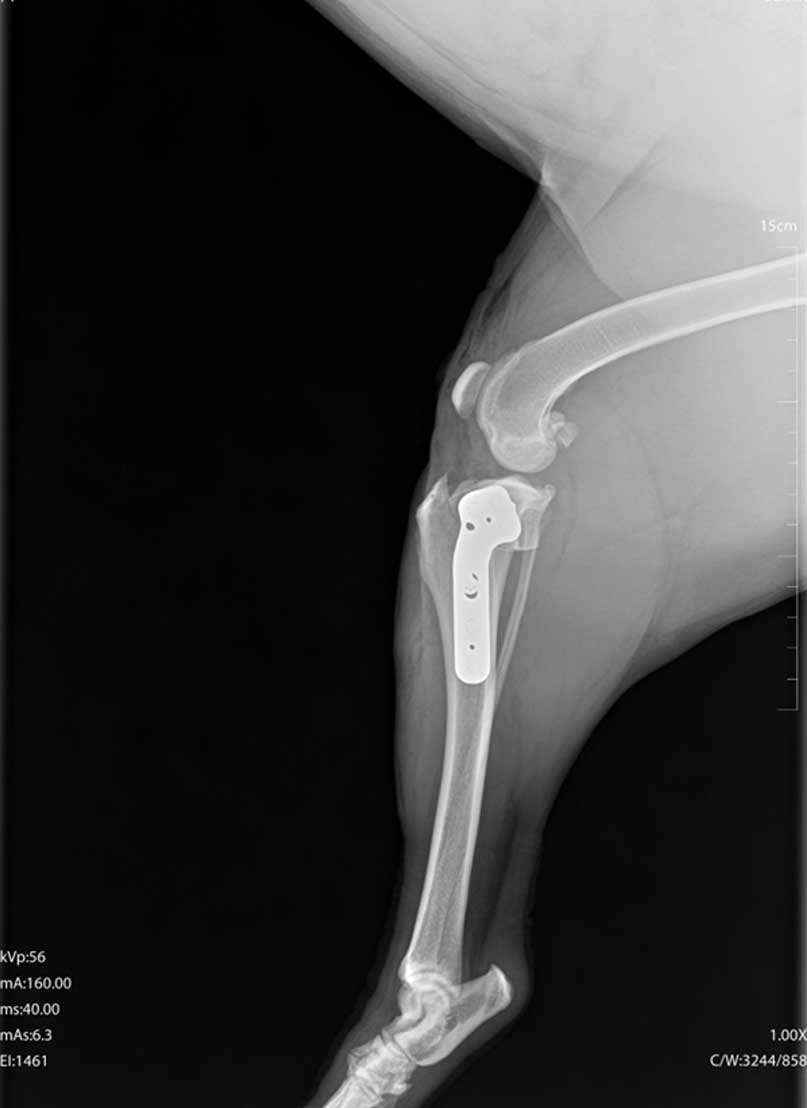

TPLO (Tibial Plateau Leveling Osteotomy) je kirurški zahvat koji se koristi za liječenje puknuća prednjeg križnog ligamenta koljena.

Tijekom TPLO operacije mijenja se kut gornje površine goljenične kosti kako bi se koljeno stabiliziralo bez potrebe za ligamentom.

Kirurg napravi kontrolirani rez na kosti, zakrene je u novi položaj i učvrsti posebnom metalnom pločicom i vijcima, time se sprječava klizanje potkoljenice pri opterećenju noge.

Većina pasa počinje opterećivati nogu unutar nekoliko dana nakon zahvata, potpuni oporavak traje otprilike 8 do 12 tjedana uz kontroliranu aktivnost i rehabilitaciju.

Prednost TPLO-a je brži i sigurniji povratak normalnom hodu, osobito kod srednjih i velikih pasa.

TPLO je danas jedna od najpouzdanijih i najčešće korištenih ortopedskih operacija u veterinarskoj medicini.